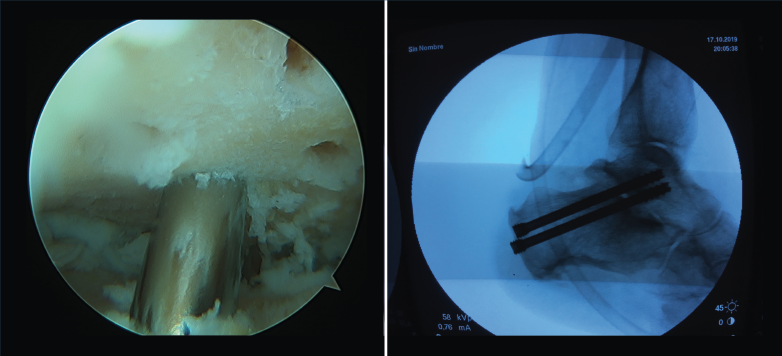

Figura 5. Plastia simple artroscópica del ligamento talofibular anterior (LTFA) con aloinjerto en paciente con inestabilidad.

- Cirugía artroscópica: lesiones osteocondrales, tratamiento artroscópico de la inestabilidad (reparación y técnicas de reconstrucción), endoscopia posterior de tobillo y tendoscopia (Figuras 4, 5, 6 y 7).